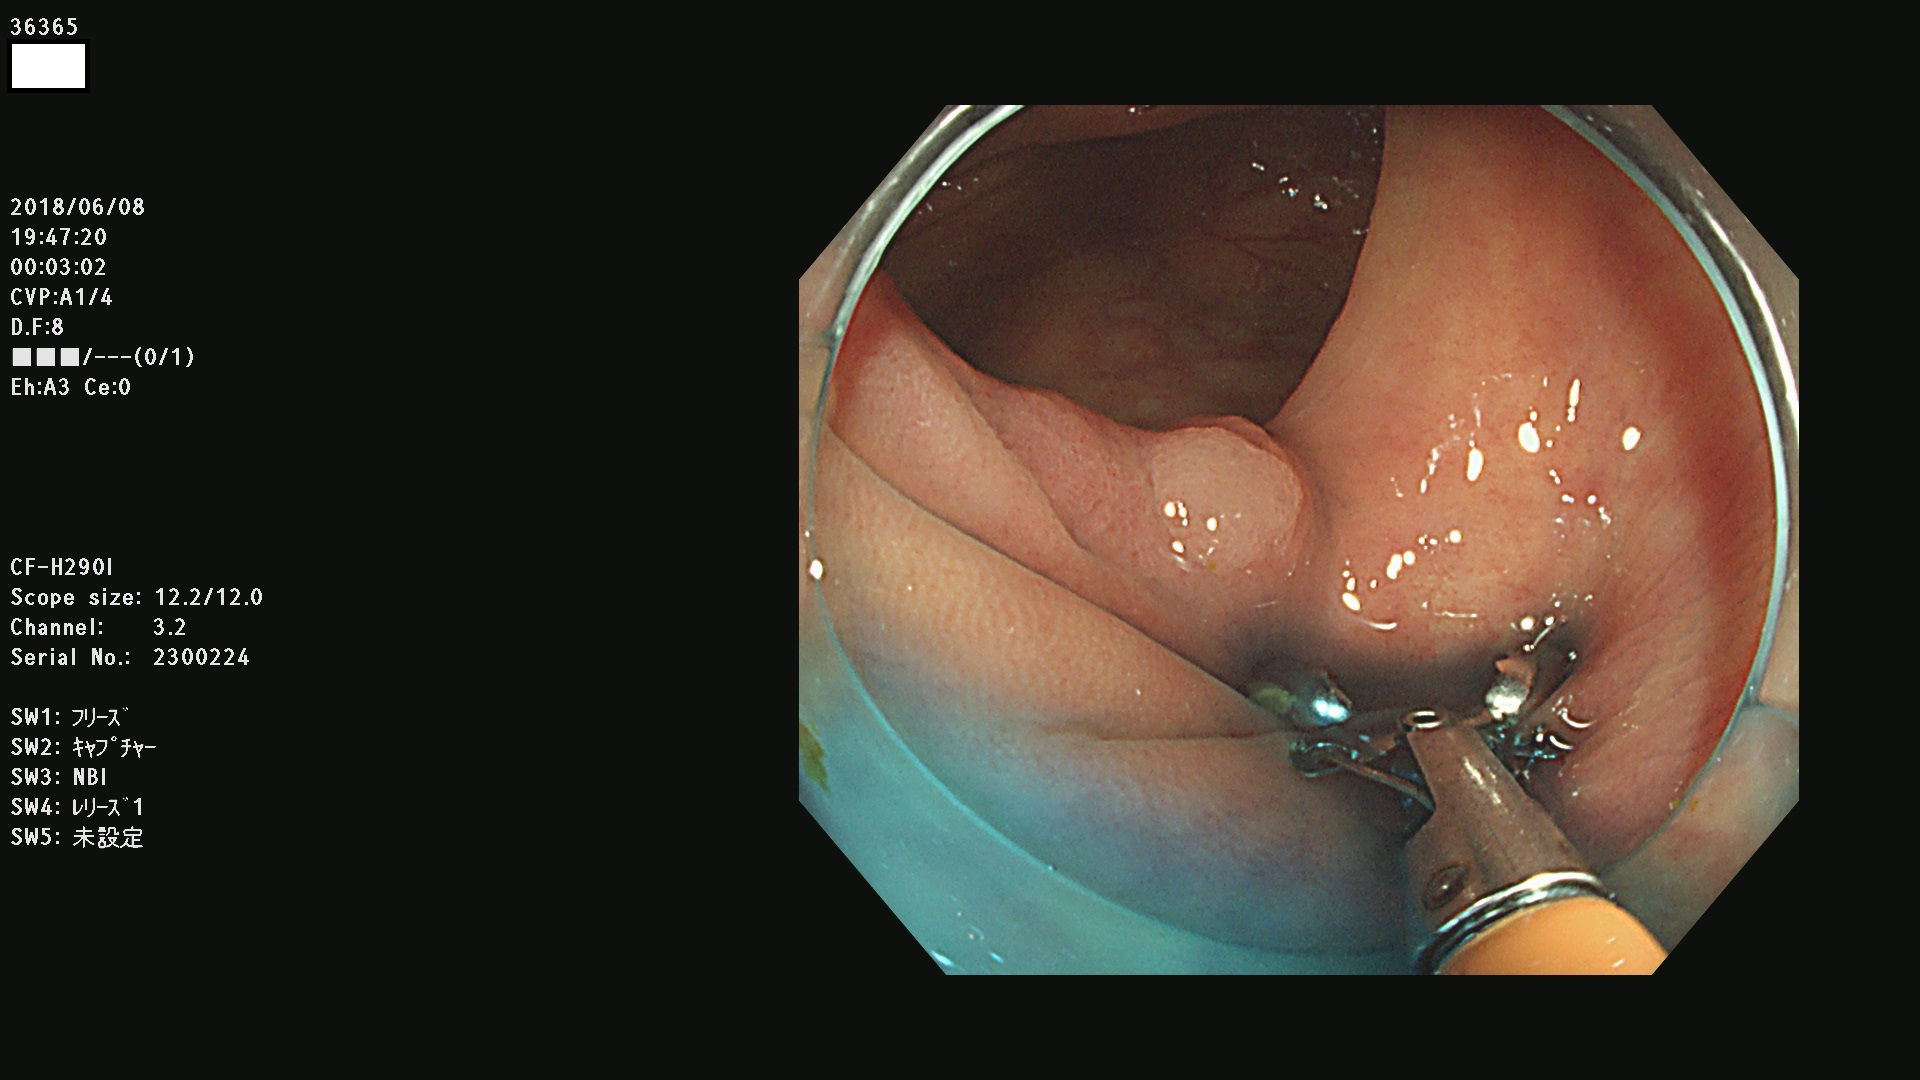

腺腫発見率 68 % (カルテ番号 36300〜36399の100名の方の検査結果で集計)大腸癌検診最新情報

以下のカルテ番号の方に腺腫(Adenoma,Group3〜5)が見つかりました(集計法)

36300 36302 36305 36306 36307 36308 36310 36311 36312 36313 36314 36315 36316 36318 36321 36322 36324 36325 36326 36327 36330 36332 36333 36334 36335(SSAPのみ) 36337 36338 36339(SSAPのみ) 36340 36341 36342(SSAPのみ) 36343 36344 36346 36348 36349 36351 36353 36354 36355(SSAPのみ) 36356 36357 36358 36359 36364 36365 36366 36367 36370 36374 36376 36379 36381 36382 36383 36384 36385 36387 36388 36389 36390 36392 36393 36395 36396 36398 36399

発見困難で危険性の高い平坦型病変(上記100名より抽出) ![]()